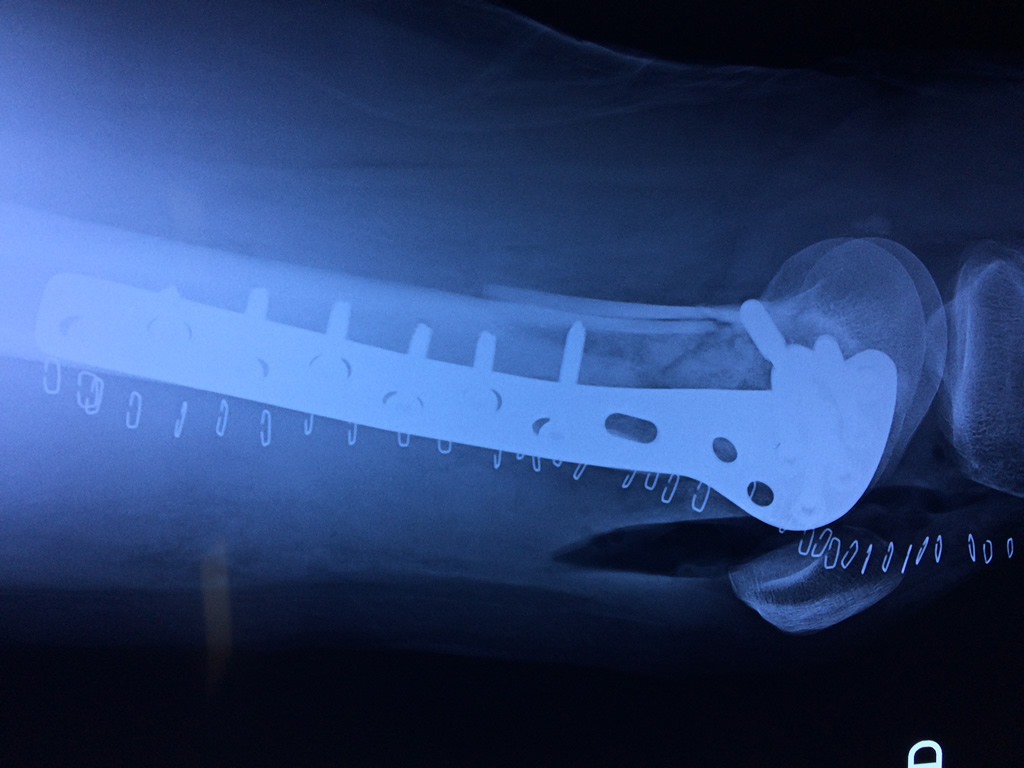

Cirugía de Tibia y Peroné